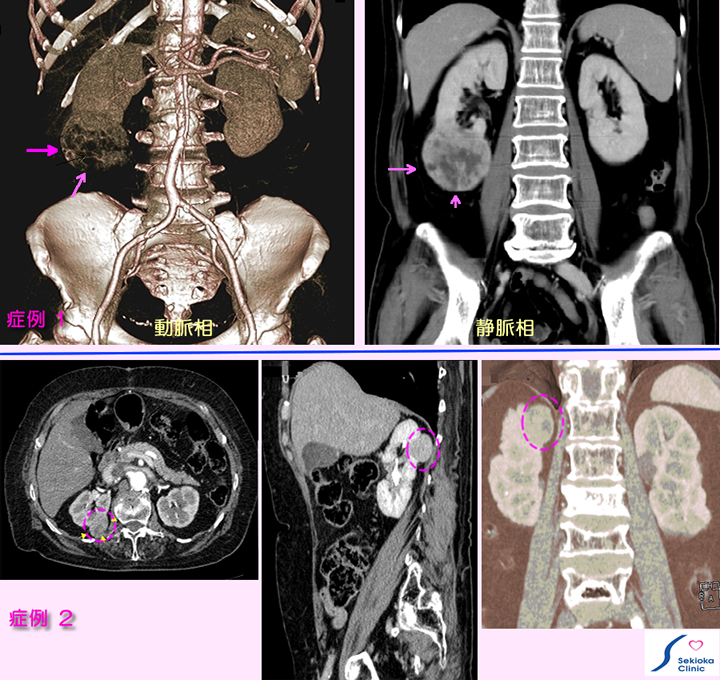

腎臓がん

血尿・痛みなどなく、腎以外の症状で検査し、偶然見つかる。症例2も自覚症状無く偶然見つかる。

診断

症例1は他の目的での腹部CT検査時、腎がん疑われ、造影MDCTで精査。右腎下極に腫瘍(矢印)を認めるが他に転移所見を認めず。症例2は血管の造影検査時、偶然見つかる。比較的小さな早期の腎臓がん(破線円内)です。

治療

手術にて摘出。手術時転移は認めず、2年無事に経過。